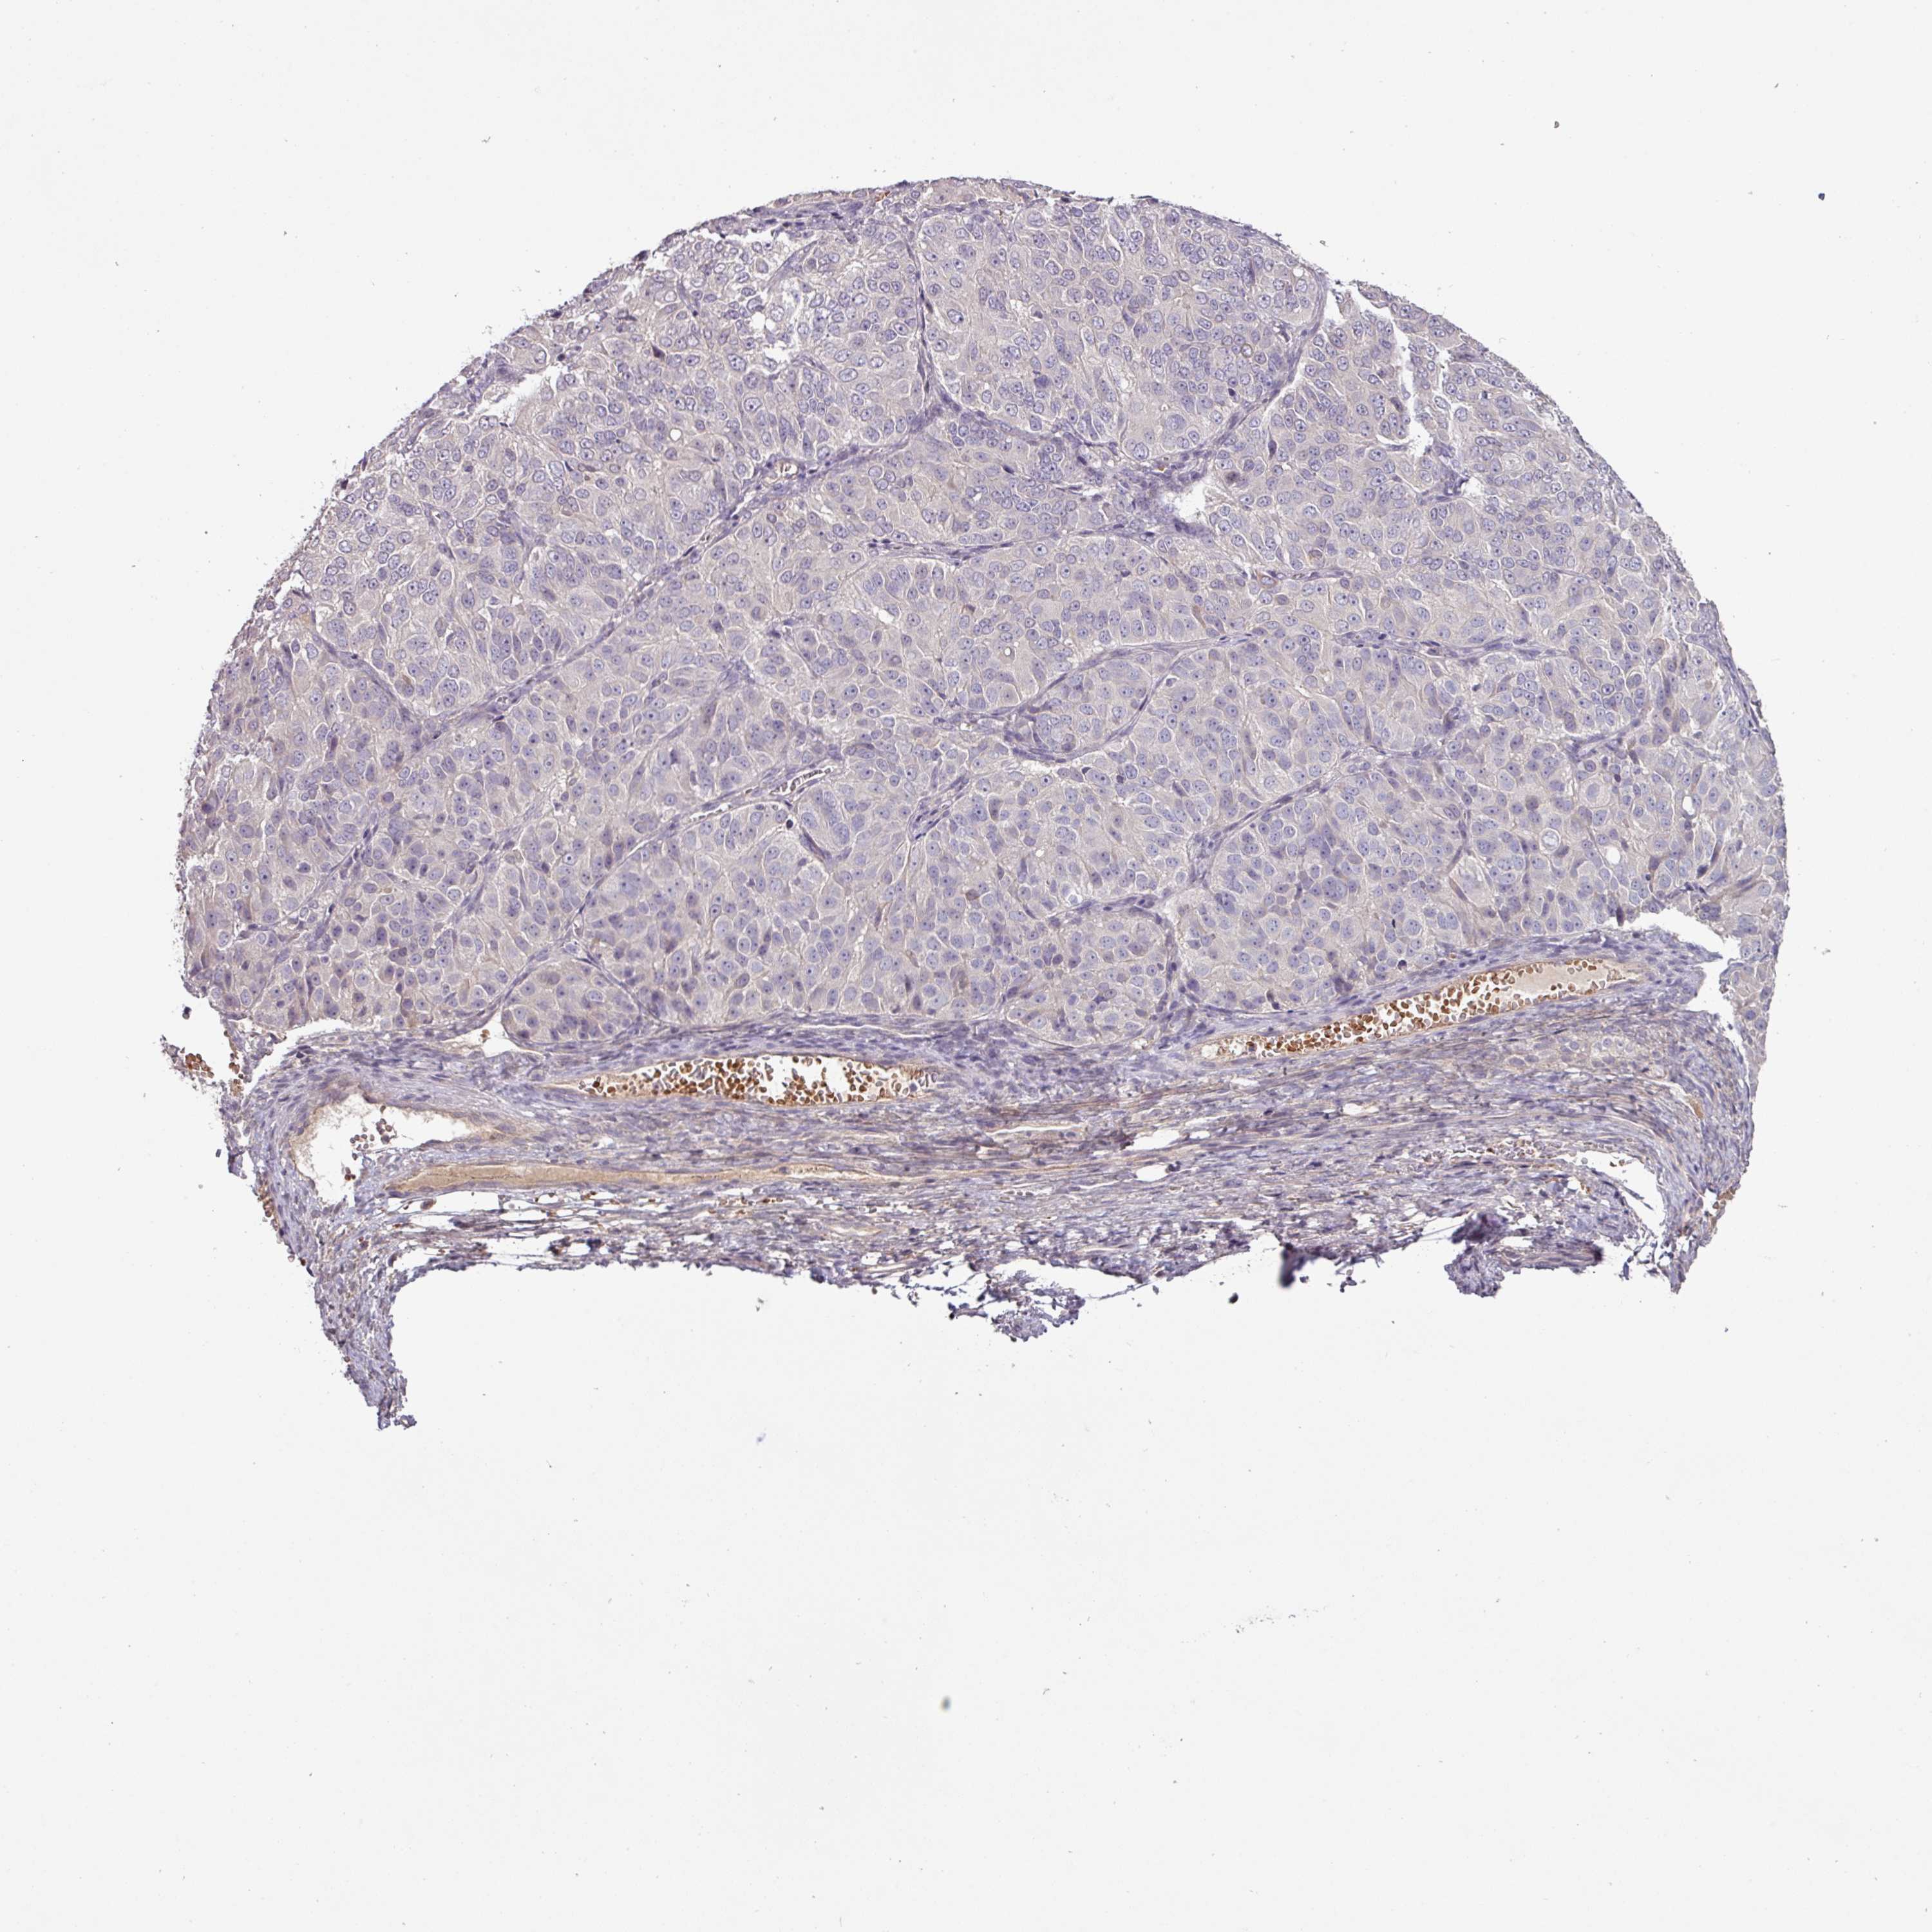

OVARIAN CANCER - Protein expressioni

A mouse-over function shows sample information and annotation data. Click on an image to view it in a full screen mode. Samples can be filtered based on level of antibody staining by selecting one or several of the following categories: high, medium, low and not detected. The assay and annotation is described here.

Note that samples used for immunohistochemistry by the Human Protein Atlas do not correspond to samples in the TCGA dataset.

Antibody stainingi

Antibody staining in the annotated cell types in the current human tissue is reported as not detected, low, medium, or high, based on conventional immunohistochemistry profiling in selected tissues. This score is based on the combination of the staining intensity and fraction of stained cells.

Each image is clickable and will lead to virtual microscopy that enables deeper exploration of all samples and also displays staining intensity scores, fraction scores and subcellular localization as well as patient and tissue information for each sample.

Antibody HPA052014

Staining

High

Medium

Low

Not detected

Intensity

Strong

Moderate

Weak

Negative

Quantity

>75%

75%-25%

<25%

None

Location

Nuclear

Cytoplasmic/membranous

Cytoplasmic/membranous,nuclear

Cystadenocarcinoma, serous, NOS

Carcinoma, NOS

Cystadenocarcinoma, mucinous, NOS

Carcinoma, endometroid